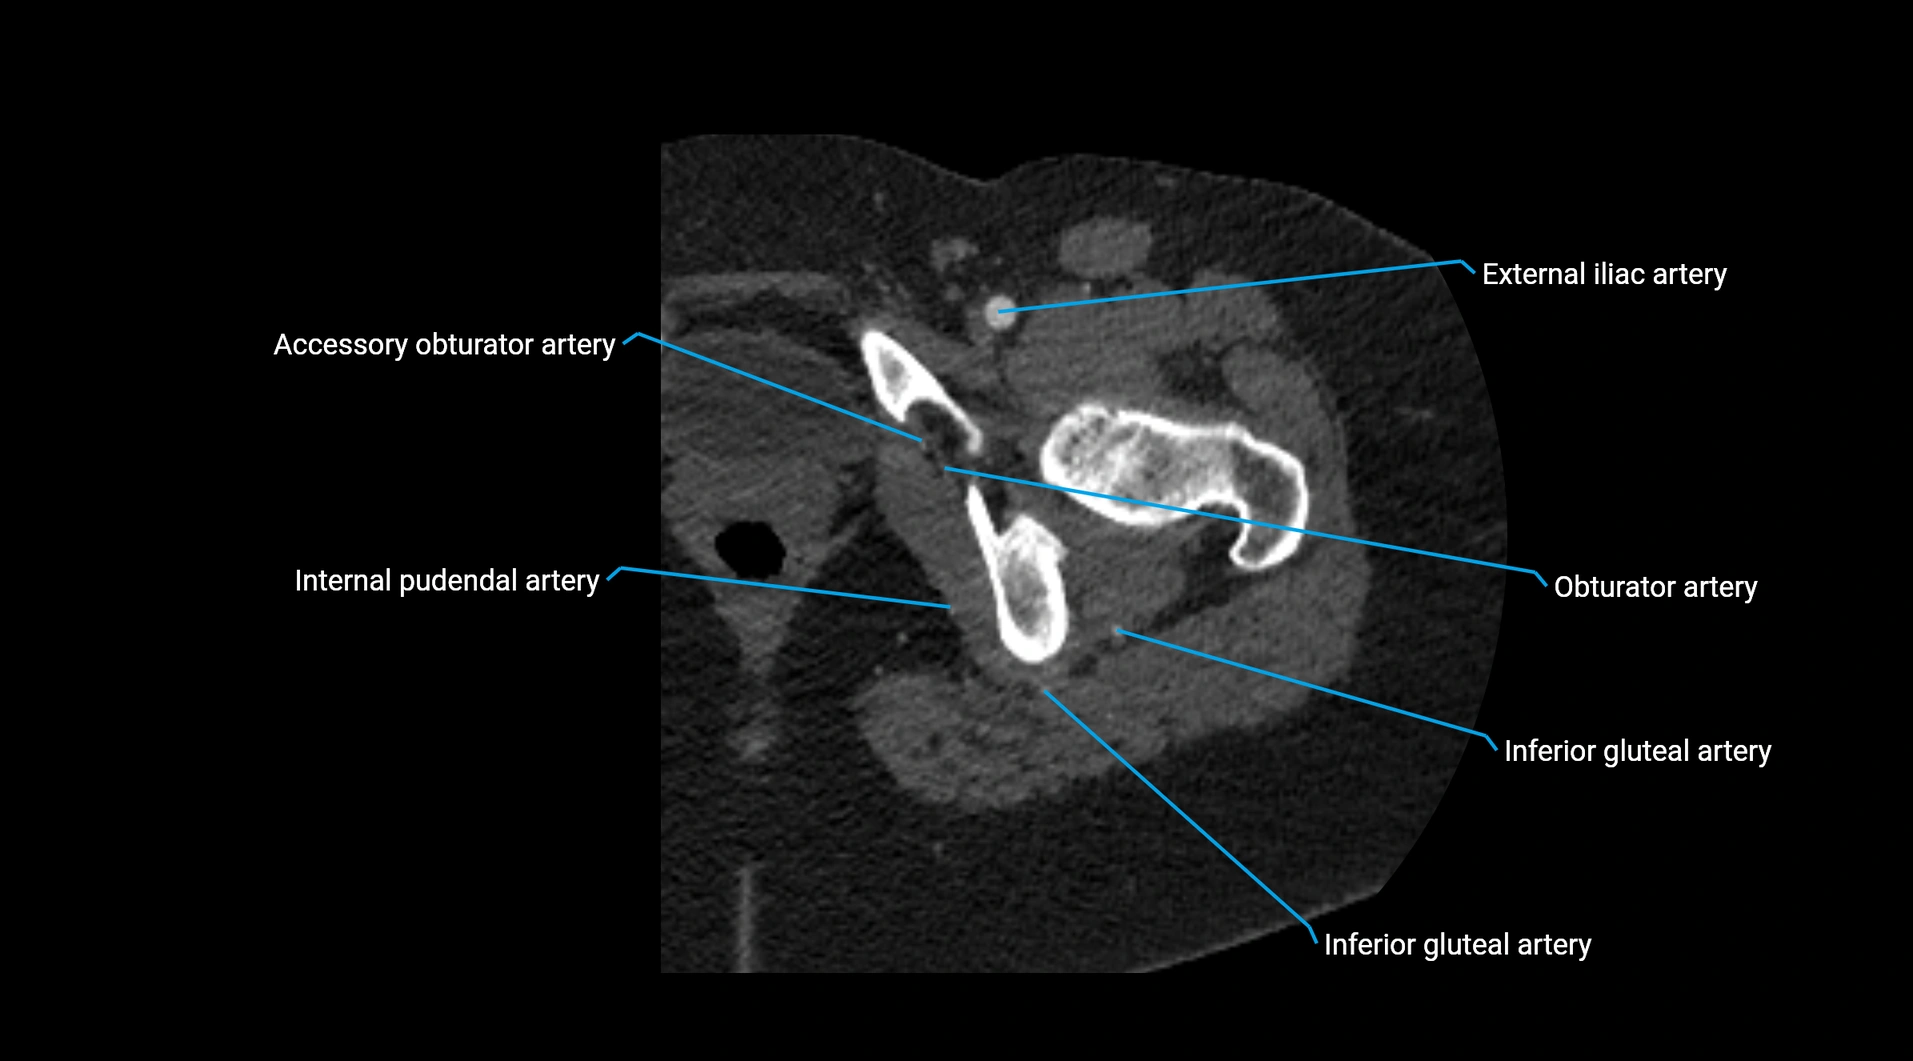

Contrast-enhanced CT (CTA):

• Gold standard for abdominal aortic imaging

• Provides excellent detail of lumen, wall, aneurysm, thrombus, and branch vessels

• Multiplanar and 3D reconstructions help in aneurysm measurement, stent graft planning, and dissection evaluation

• Detects acute rupture, traumatic injury, or occlusion with high sensitivity